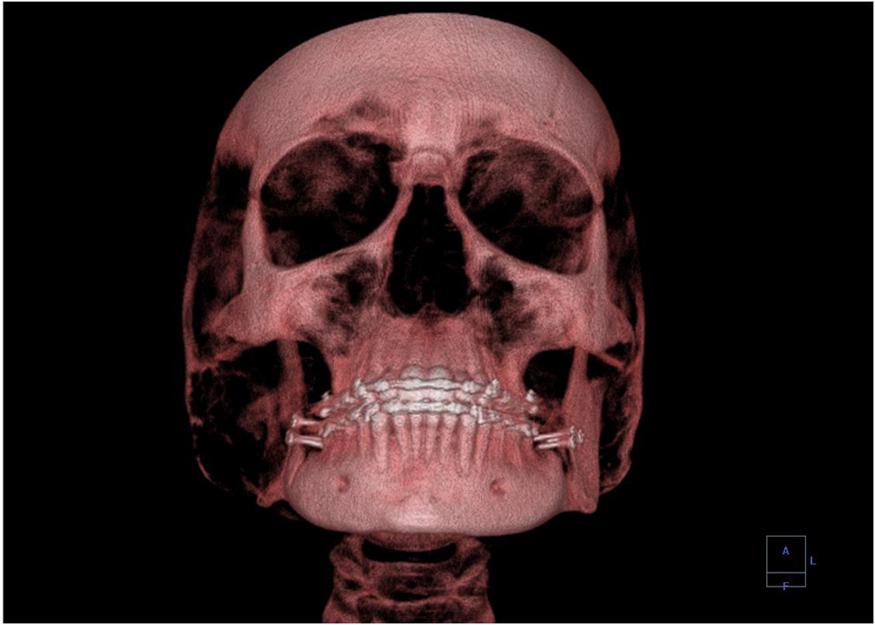

A standard X-ray gives only a two-dimensional view of the object. Dense bones might hide images of soft tissue or organs. If you took another X-ray from the side of the person—the first one being from the front—you would gain additional information. While shadow images are sufficient in many applications, far more sophisticated images can be produced with modern technology. Figure 13.27 shows the use of a computed tomography (CT) scanner, also called computed axial tomography (CAT) scanner. X-rays are passed through a narrow section, called a slice, of the patient’s body, or body part, over a range of directions. An array of many detectors on the other side of the patient registers the X-rays. The system is then rotated around the patient and another image is taken, and so on. The X-ray tube and detector array are mechanically attached and so rotate together. Complex computer image processing of the relative absorption of the X-rays along different directions produces a highly detailed image. Different slices are taken as the patient moves through the scanner on a table. Multiple images of different slices can also be computer analyzed to produce three-dimensional information, sometimes enhancing specific types of tissue, as shown in Figure 13.28. G. Hounsfield (UK) and A. Cormack (United States) won the Nobel Prize in Medicine in 1979 for their development of CT.

A 3-D image showing a human skull from the front.

Figure 13.28 This three-dimensional image of a skull was produced by CT, involving analysis of several X-ray slices of the head. (Emailshankar, Wikimedia Commons)